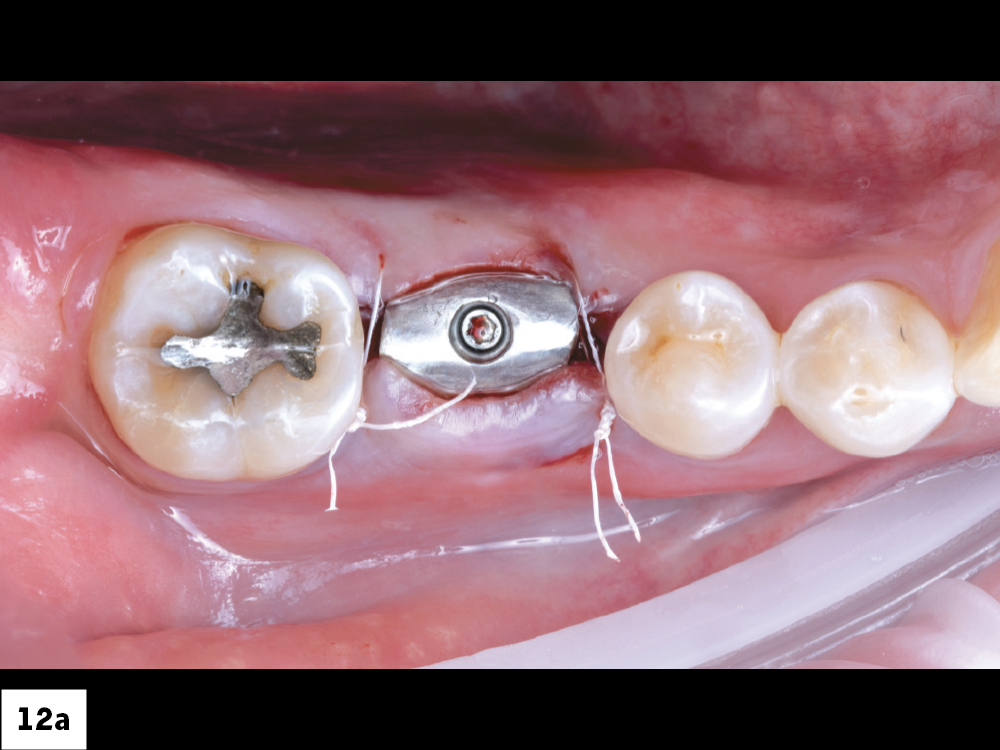

Figures 12a, 12b: Two interrupted sutures were placed using Biotex™ Non-resorbable PTFE Sutures (available through Glidewell Direct), one on the mesial and one on the distal.